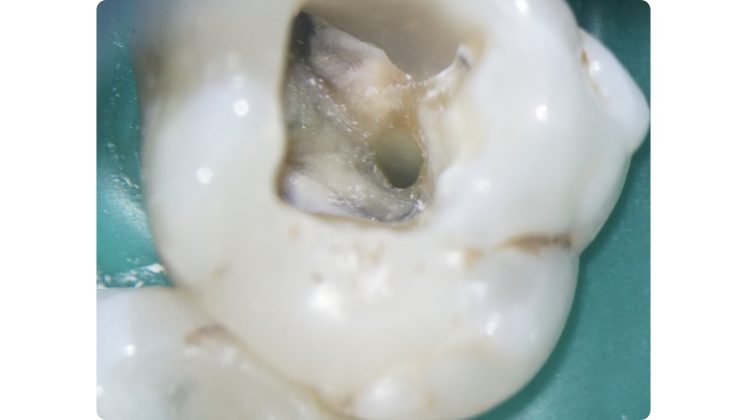

La regola della polvere dentinale

Qualora invece l’ostruzione si estendesse più in profondità, la regola della polvere dentinale può servire come guida per il clinico. Questa regola trae il suo fondamento da una delle leggi di Krasner e Rankow7, quella del cambio di colore.

Il sistema canalare è sempre contenuto in un’area più scura rispetto alle pareti canalari e quindi l’azione di avanzamento è guidata proprio da questo assunto cromatico.

Consumando lentamente dentina in direzione apicale (a secco, a basso numero di giri, raffreddando con la siringa ad aria) pochissimi decimi di millimetro per volta si manterrà la corretta centratura all’interno della radice e si potrà visualizzare ad un certo punto una traccia bianca: non si tratta altro che di polvere dentinale prodotta dall’azione dello strumento rotante che si deposita in maggiore quantità proprio in corrispondenza della traccia dell’orifizio.

Lo strumento ideale per avanzare alla ricerca del canale è ancora una volta Endotracer. Il gambo lungo (disponibile anche nella versione 34 mm, oltre che 31 mm) consente di poter avere sempre controllo visivo sull’avanzamento.

I diametri utilizzati vengono scelti in base alla profondità: via via che si procede apicalmente è necessario ridurre il diametro e anche la velocità di utilizzo, oltre che fare pause di controllo sempre più frequenti.

Questa azione di consumo selettivo della dentina può rendere visualizzabile in tempi molto brevi la traccia “bianca” di polvere depositata sull’orifizio; qualora invece i primi passaggi non avessero reso possibile la localizzazione è opportuno alternare irrigazione con ipoclorito di sodio e asciugatura per poi ripartire con un nuovo ciclo di escavazione (Figure 27-33).

Una volta localizzata la traccia del canale è necessario cercare di sondarlo anche per pochi millimetri con un micro opener o un K file di piccole dimensioni 06 o 08.

In questa fase di esplorazione va riposta molta attenzione nell’evitare di ostruirsi di nuovo la strada in direzione apicale: questo è possibile grazie a ripetuti lavaggi e alternanza di tentativi di sondaggio manuale senza forzare e affrettare la discesa fino a lunghezza di lavoro. A differenza degli inserti ultrasonici che tendono a creare un invito spesso appuntito in direzione apicale e ad annullare almeno parzialmente le tracce cromatiche, l’utilizzo di strumenti rotanti strategici come Endotracer preserva questi fondamentali punti di riferimento e anzi facilita l’accumulo di detriti dentinali proprio dove c’è una naturale depressione, vale a dire il lume canalare.